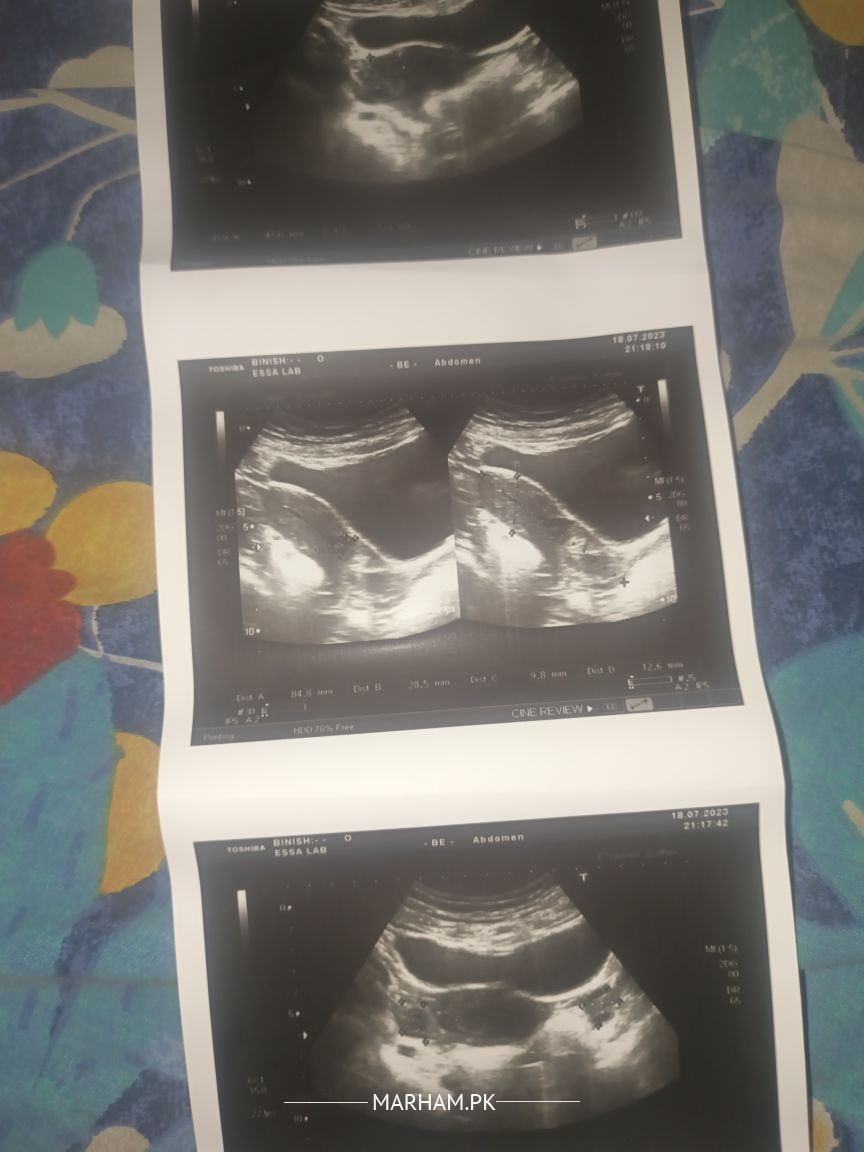

Talk to General Physician on Scar Syct Small Collection ?

Asking For Self, Male 33, Karachi

please koi Rehm kro Kiya aya report pr bhut takleef me hun

for proper diagnosis and management need to be visited by a senior general physician specialist

visit to specialist physician

Does the cyst hurt all the time of the day or only during menstrual periods?

Your wife should consult her own gynaecologist or search for a competent gynaecologist. The gynaecologist can determine if it is a post surgical complication,?an infected cyst? ,,or endometrioyic cyst.

Treatment will be accordingly.